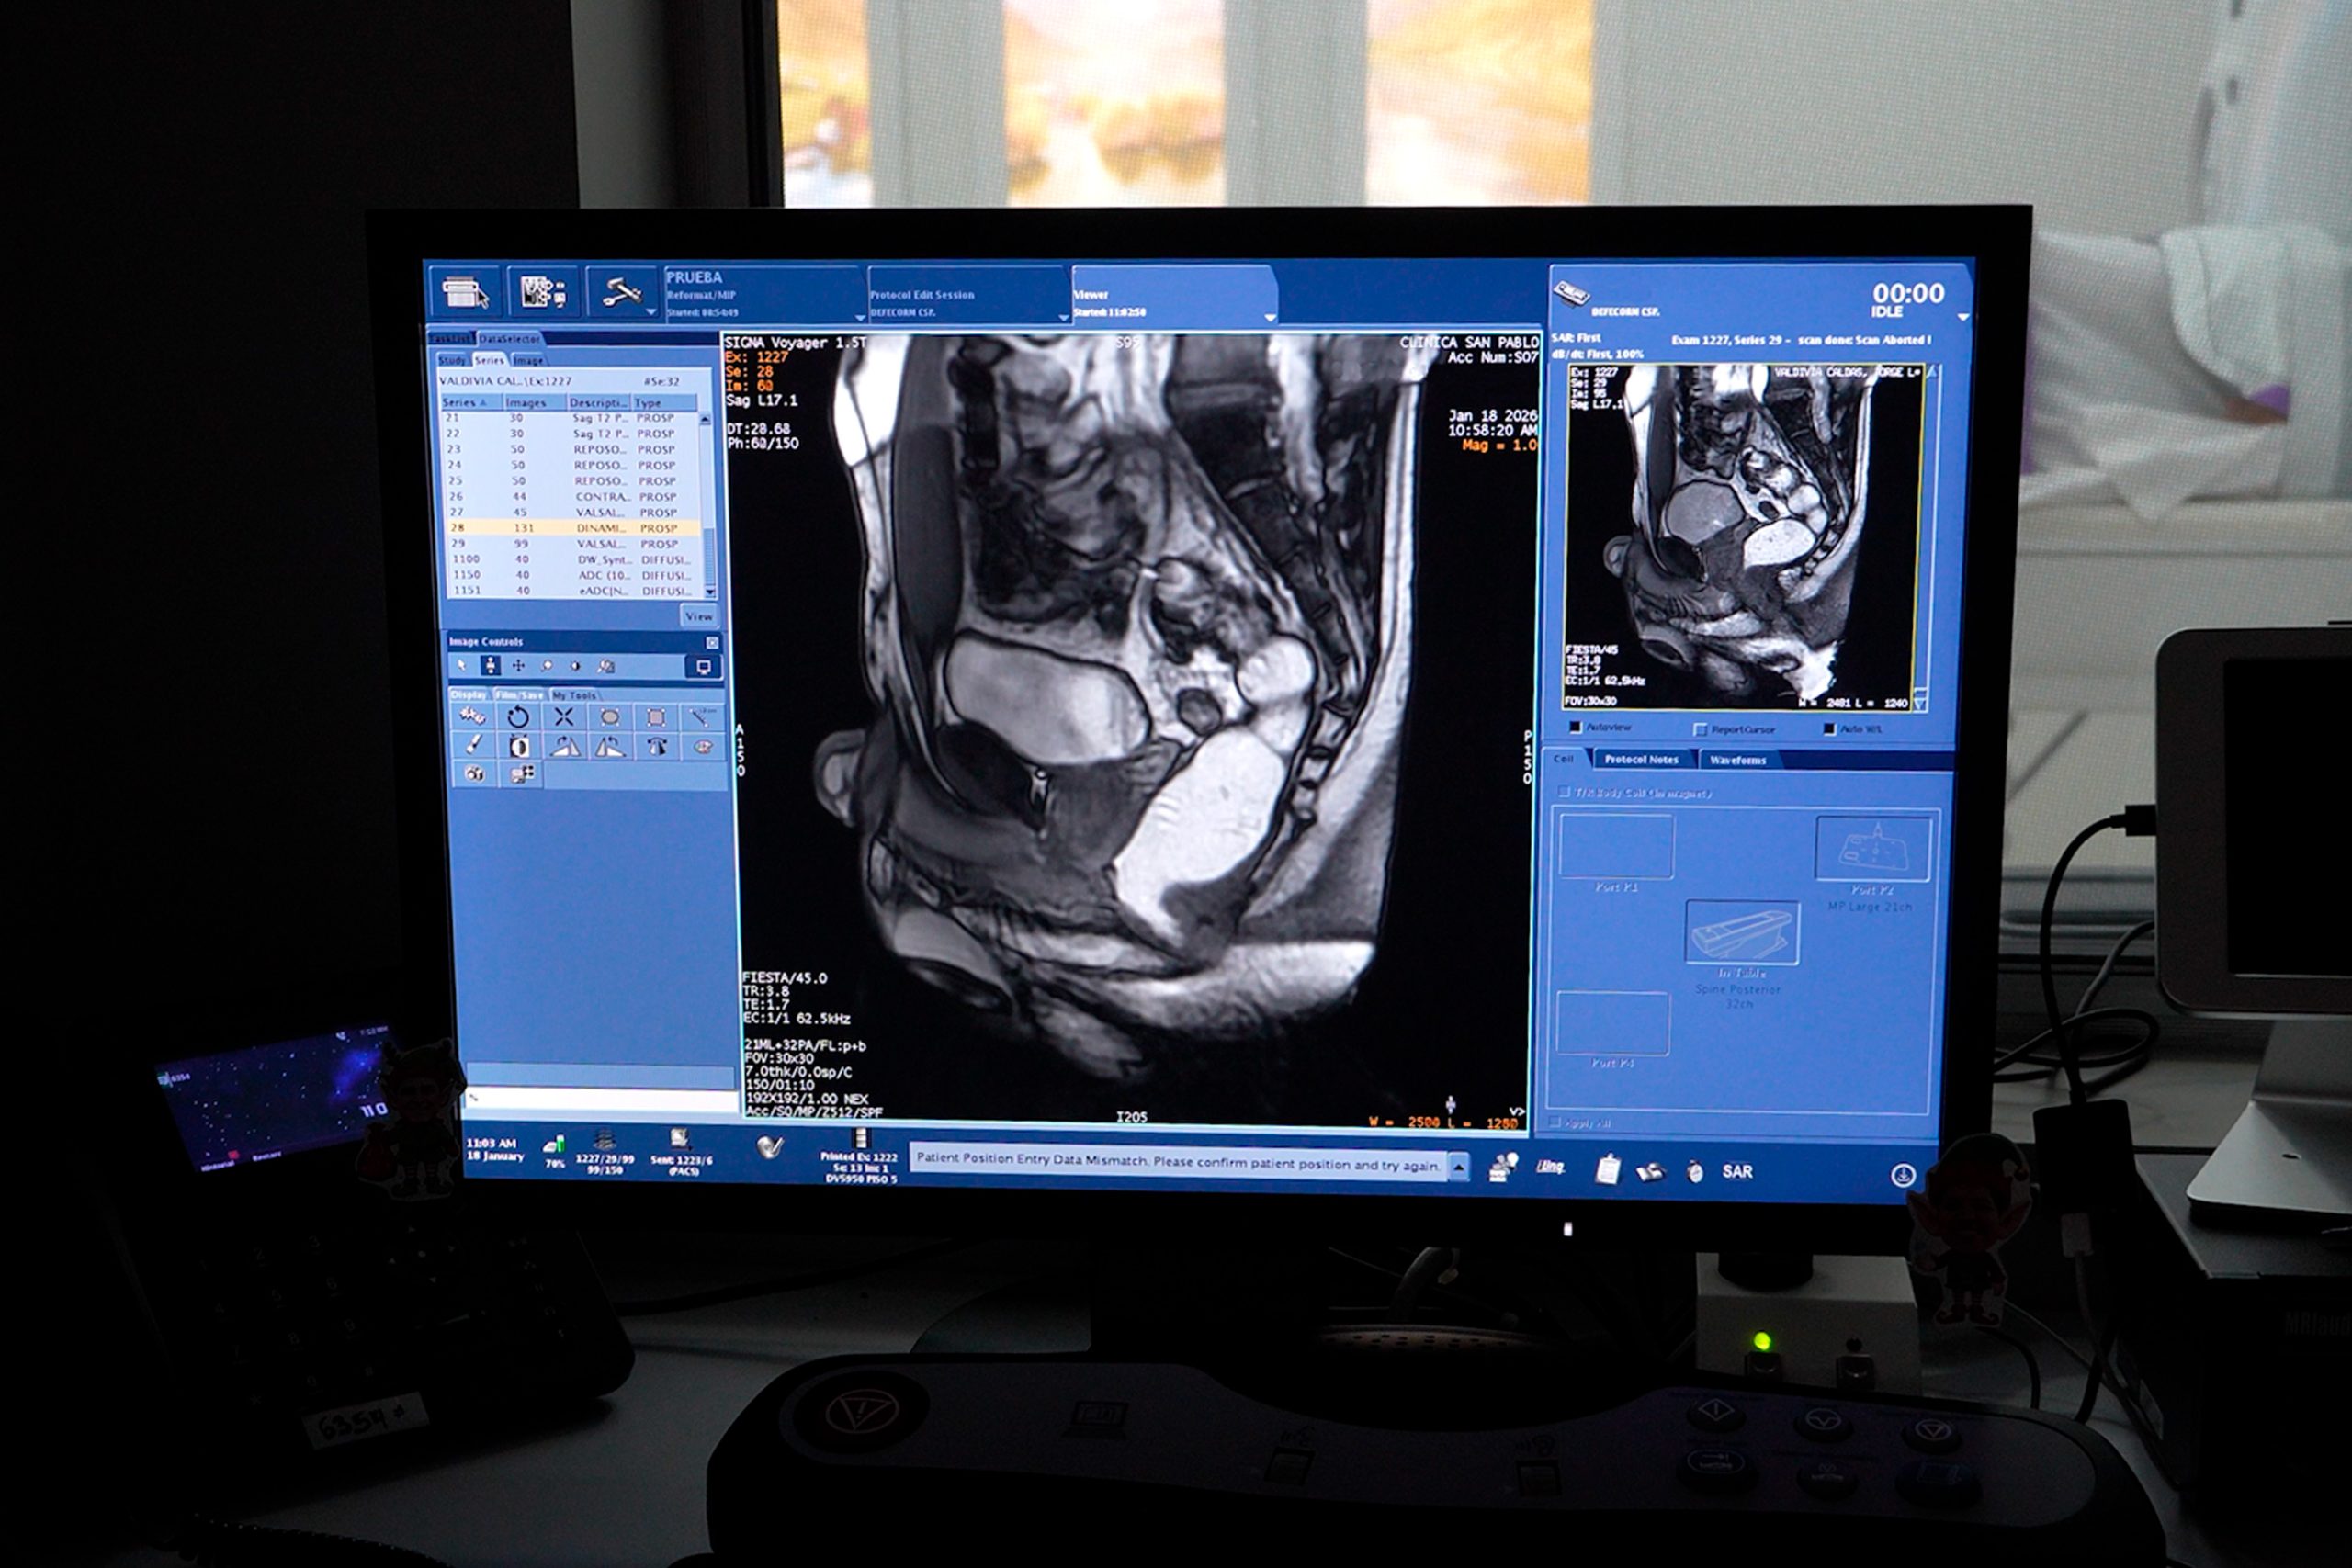

La Clínica San Pablo La Victoria, en alianza con Tomomedic, marca un hito en la medicina especializada al incorporar la Resonancia Magnética Dinámica del Piso Pélvico (también conocida como defecografía por resonancia). Este estudio de alta complejidad permite evaluar de forma integral y funcional las alteraciones del suelo pélvico, una zona clave para la calidad de vida tanto de hombres como de mujeres.

A diferencia de una resonancia convencional, este es un examen de diagnóstico por imágenes especializado que evalúa los órganos pélvicos en movimiento y en tiempo real.

Mientras que un estudio estático solo toma «fotos», la resonancia dinámica analiza el comportamiento de los músculos y órganos durante maniobras funcionales como: